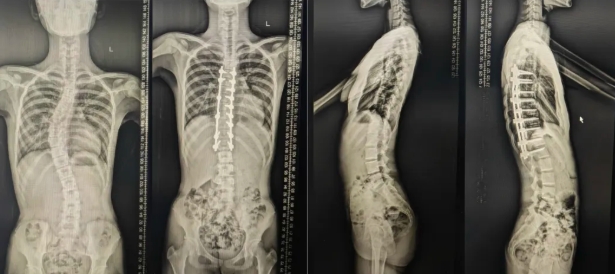

15岁的少女晓晓(化名)的脊柱Cobb角已达72度,X光片上呈"S"形的弯曲弧度导致胸腔严重受到压缩;另外两名孩子的病情同样不容乐观,除了存在40°-60°的侧弯,同时伴有胸椎前凸等复杂侧弯病变。 “这些孩子如果再不手术,会出现呼吸功能、神经功能损害等严重后果。”邱勇院士介绍,在过去数十年的临床中,他见过太多因延误治疗而永远失去矫正机会的病例。孩子的母亲回忆发病过程,说女儿三年来不愿穿紧身衣,体育课成绩也受影响,由于病情发现的较晚,虽然佩戴了近2年的矫形支具,病情仍然持续发展。

部分患者术后X光检查

邱勇团队蒋军教授介绍,根据术后透视结果,3名患者的脊柱侧弯角度均已明显矫正,术后俯卧位测量结果,提示最明显的一个孩子身高将提高接近5cm。这些孩子的改变,远不止脊柱X片上的角度变化,更是对未来健康生活的希望。